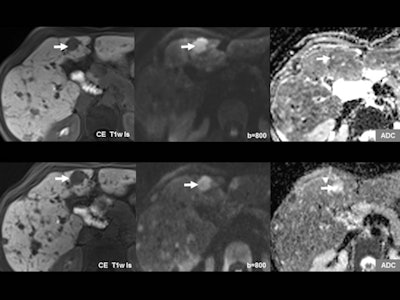

Diffusion-weighted imaging (DWI) can give information beyond that provided by morphological scans. In this case, liver metastasis of a neuroendocrine tumor is shown before (upper row) and after (lower row) therapy. While no change is seen on the contrast-enhanced scans (left), DWI and apparent diffusion coefficient (ADC) (middle and right) show an increase in diffusion that indicates response to therapy. Images courtesy of Dr. Christine Schmid-Tannwald, Ludwig Maximilian University, Munich.

Diffusion-weighted imaging (DWI) can give information beyond that provided by morphological scans. In this case, liver metastasis of a neuroendocrine tumor is shown before (upper row) and after (lower row) therapy. While no change is seen on the contrast-enhanced scans (left), DWI and apparent diffusion coefficient (ADC) (middle and right) show an increase in diffusion that indicates response to therapy. Images courtesy of Dr. Christine Schmid-Tannwald, Ludwig Maximilian University, Munich.Structured reporting. The second way that precision medicine would be supported is through structured reporting, which can help clinicians harvest the specific information obtained by imaging.